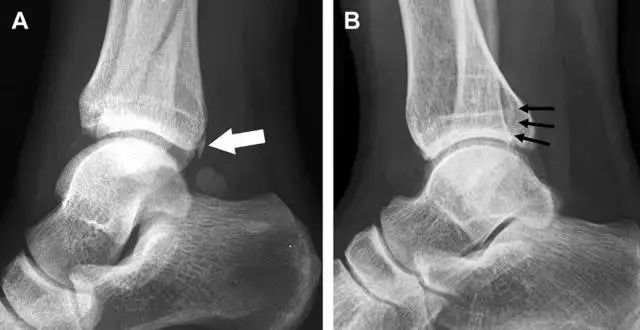

膝关节容易漏诊的骨折,大多伴发于韧带损伤,如前后交叉韧带、关节囊韧带、弓状韧带、侧副韧带等。急诊处置膝关节外伤时,在 X 线片上需要特别留意各韧带起止点附近骨质的完整性,发现骨折的迹象需高度怀疑韧带结构损伤的可能。以 Segond 骨折为例,伴发前交叉韧带的几率在 90% 以上。急诊科医生常遇到的一个问题是:踝关节疼痛。对于这类患者,想要分辨是否存在骨折,X 线检查是主要手段。然而,由于各种原因,有些踝部骨折非常容易漏诊。

首先,来看踝关节骨折的高危区(图 1)。

图 1 踝部探查模板。阅片时,需对踝关节的前后位片(A)、内旋转位片(B)侧位片(C)仔细阅读,逐一详细排查。上图中的骨折:1. 内踝骨折,2. 外踝骨折,3. 胫骨结节骨折,4. 胫骨后踝骨折,5. 距骨骨软骨骨折,6. 距骨外侧突骨折,7. 距骨后突骨折,8. 距骨舟骨关节背侧骨折,9. 跟骨前突骨折,10. 跟骨骨折嵌插入趾短伸肌,11. 第五跖骨底骨折。

16

胫骨后踝骨折

涉及到三角韧带和外侧副韧带(LCL)的复杂性骨折常常不难发现,尤其是存在表面软组织肿胀时。然而,后胫腓韧带牵拉引起的胫骨后踝骨折则很难发现。这些骨折大小不一(图 2),却很重要,因为他们常与胫骨远端螺旋骨折有关,或者是三踝骨折的一部分。

图 2 胫骨后踝骨折。A 侧位片示来源于胫骨后踝的一个小骨折碎片(箭头),因踝部扭伤导致;B 另一位跖屈损伤的患者,侧位片示一个大骨折块(箭头)。

17

胫骨结节骨折

Tillaux 骨折,是足外旋外展时,胫腓前韧带牵拉引起的一种胫骨结节撕脱性骨折。斜位片上可见典型表现(图 3)。

图 3 摔倒后胫骨结节骨折。A 正位片示一细小斜型骨折线(箭头);B 侧位片示正常;C 冠状位 CT 三维成像更清晰地显示了骨折线和骨折块大小(空箭头);D 矢状位 CT 多维重建图像示骨折位置(箭头)。